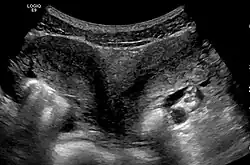

Besides a physical examination, the physician will need imaging techniques to determine the character of the malformation: gynecologic ultrasonography, pelvic MRI, or hysterosalpingography. A hysterosalpingogram is not considered as useful due to the inability of the technique to evaluate the exterior contour of the uterus and distinguish between a bicornuate and septate uterus. In addition, laparoscopy and/or hysteroscopy may be indicated. In some patients the vaginal development may be affected.